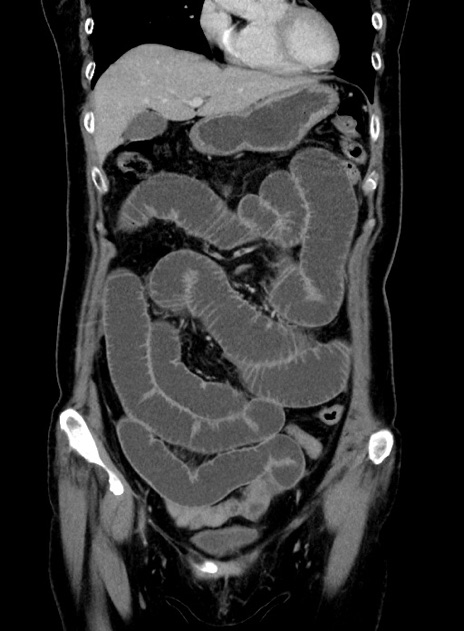

症例9(冠状断像)

【症例】 60歳代女性

【主訴】むかつき、みぞおちの痛み

【現病歴】3日前よりむかつきがあり、食事がとれない。

【既往歴】糖尿病

【身体所見】発熱なし、心窩部圧痛軽度あるも、腹膜刺激症状なし。

【データ】WBC 7400、CRP 1.92